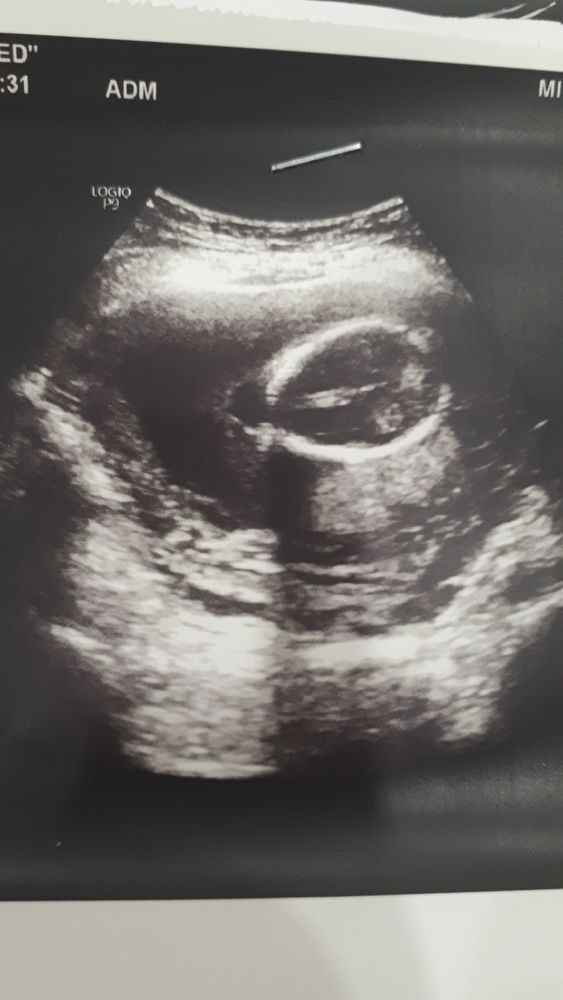

Давайте поугадываем, пока анализ на пол не пришёл)))

Как думаете? Мальчик или девочка?

Первое фото в 12 недель, а второе - в 15, видимо наша маленькая жопка 🤣🤣🤣 Полагаю узист хотел этим что-то показать🤣

Belka, ну яички выглядят по-другому. А 70% дали,что мальчик? Ну вот по этому снимку явная девочка🤷а когда анализ на кровь будет готов?